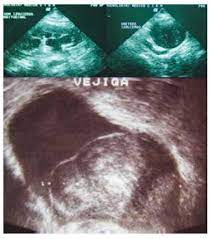

Leiomioma vesical

Diagnóstico

El diagnóstico definitivo lo obtendremos mediante el estudio histológico. Macroscópicamente se observa un tumor sólido, elástico, cubierto por mucosa vesical normal, bien delimitada, de color blanquecino.